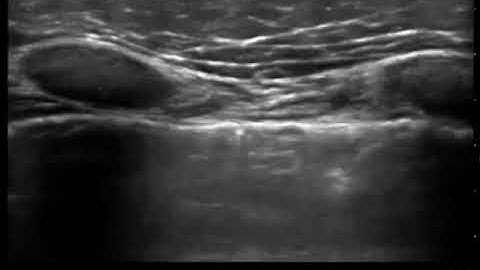

Lung Sliding with Linear Transducer